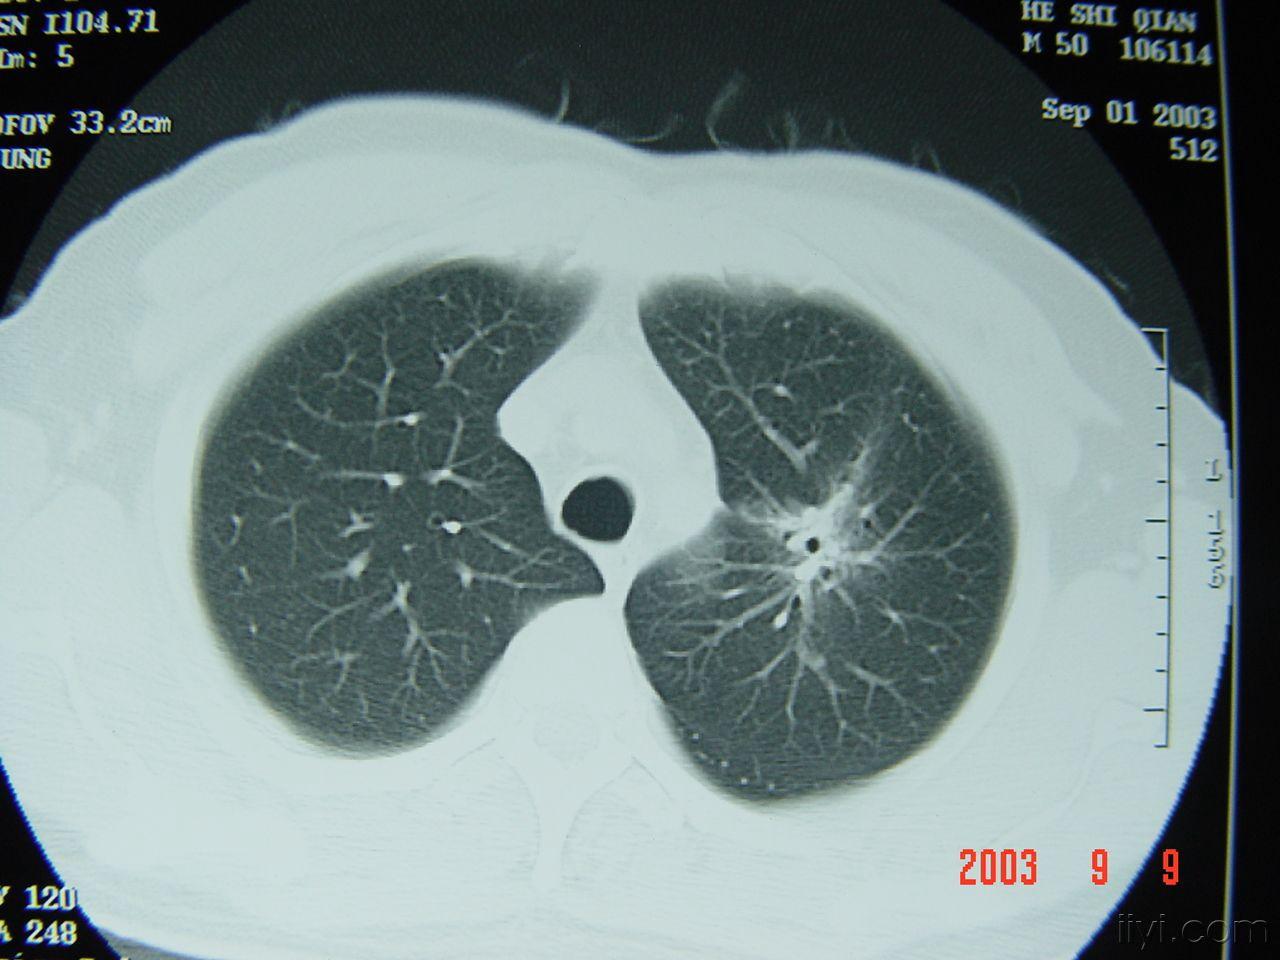

肺癌影像图片早期,肺癌影像图片晚期

肺癌- 医学影像学讨论版 - 爱爱医医学论坛

【病例】小细胞肺癌1例ct影像特征

肺癌影像图片

肺癌ct图片